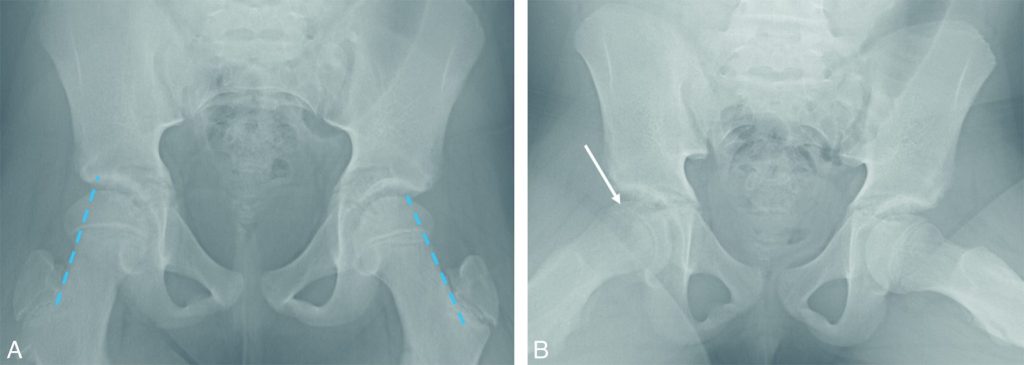

La radiographie du bassin de face est d’interprétation délicate au début en cas de faible déplacement de la tête fémorale ; l’incidence de profil est indispensable car elle objective le déplacement en dedans et vers le bas du noyau fémoral. Les anomalies sur l’incidence de face sont plus subtiles, témoignant de ce glissement : le noyau épiphysaire peut apparaître diminué de hauteur, la ligne tangente à la partie supérieure du col fémoral (ligne de Klein) ne coupe plus l’épiphyse (signe inconstant), présence d’un aspect irrégulier, élargi et incurvé du cartilage de conjugaison avec augmentation de la distance par rapport au côté controlatéral entre le pôle supérieur du noyau épiphysaire et le cartilage de croissance (flèche basi-capitale), témoin de l’éloignement du noyau épiphysaire (figure 114.4).

Fig. 114.4 Boiterie droite d’apparition récente sans fièvre chez un enfant de 10 ans en surpoids.

La radiographie de bassin de face (A) est normale : la ligne de Klein (trait en pointillé), tangente à la corticale supérieure du col fémoral, coupe de façon symétrique les épiphyses fémorales proximales. Sur le cliché de profil (B, incidence de Lauenstein), l’épiphyse fémorale proximale droite a basculé en bas et en arrière avec un décroché antérieur entre l’épiphyse et la métaphyse (flèche). Ce cas illustre l’importance de réaliser un cliché de profil additionnel pour le bilan d’une boiterie car le cliché de face peut être normal.

Source : CERF, CNEBMN, 2022.